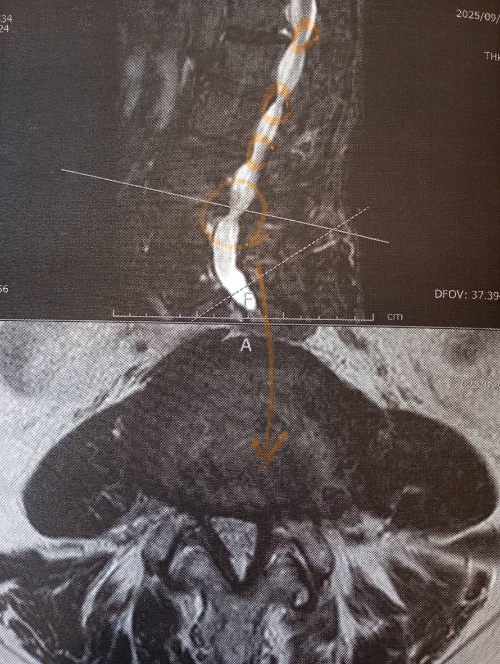

白く映っている部分が脊髄神経で数か所狭くなっている箇所が見られます。変形狭窄とヘルニアによる脊髄神経(もしくは位置的には馬尾神経)圧迫があります。

神経の圧迫があると画像では判断します。(臨床症状と一致)